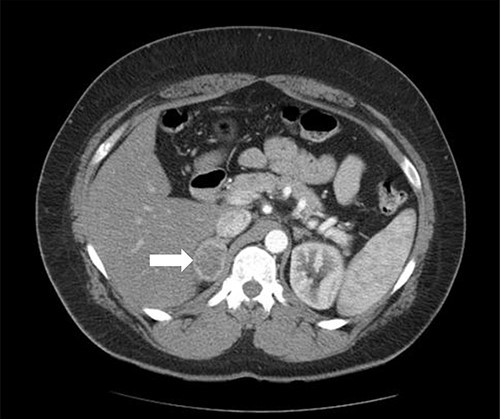

A 55-year-old male, with a BMI of 40, was referred to our surgical clinic at a governmental/academic hospital after being investigated at endocrinology department. His medical history was significant for insulin-dependent DM, uncontrolled HTN on four medications, chronic kidney disease and ischemic heart disease with multiple coronary stents on antiplatelets. A biochemical workup showed an elevated serum aldosterone of 100 ng/dl, elevated serum renin of 109 uIU/ml and elevated urinary ARR of >7000 mg/g. Serum potassium and sodium levels were within normal limits. A CECT of the abdomen and pelvis confirmed an isodense right adrenal focal lesion measuring 1.7 × 1.6 cm in pre-contrast phase, with enhancement on contrast phase followed by rapid washout, concluding a diagnosis of Conn’s syndrome (Fig. 2). Peri-operative optimization of blood pressure/cardiac status and management of anticoagulation were done through cardiac consultation. Due to his cardiac status, the patient was labeled as high risk for peri-operative cardiac events. A specialized cardiac anesthetist was consulted to perform the anesthesia.

Axial CT of the abdomen showing the right adrenal mass in Patient 2 (white arrow).